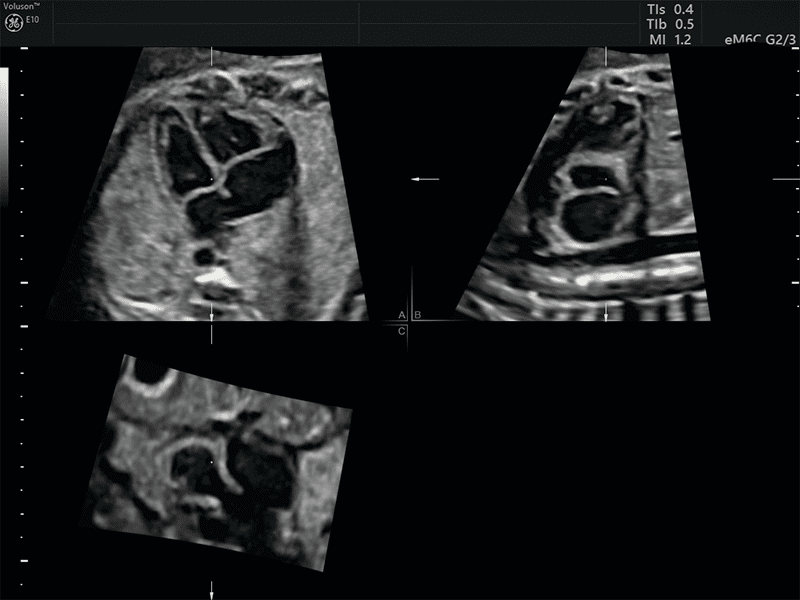

STIC: Per l’acquisizione 3D del cuore fetale, viene applicato un sofisticato algoritmo per la gestione e soppressione della distorsione causata dal movimento dei tessuti materni e fetali. Le immagini tomografiche sono riorganizzate in base alla fase del ciclo cardiaco e il data set 3D viene generato con solo immagini tomografiche nella stessa fase di ciclo cardiaco.

SonoVCAD Heart: strumento avanzato, basato sulla tecnologia Volume Ultrasound, CHE aiuta nella visualizzazione automatica delle scansione degli outflow cardiaci partendo dal volume data set acquisito. Permette una ricostruzione completa e automatizzata, relativa all’esame cardio fetale seguendo le linee guida delle società scientifiche AIUM, ACOG, ACR e ISUOG.

Semplicemente con due click il sistema è in grado di effettuare l’analisi e proporre le principali proiezioni.